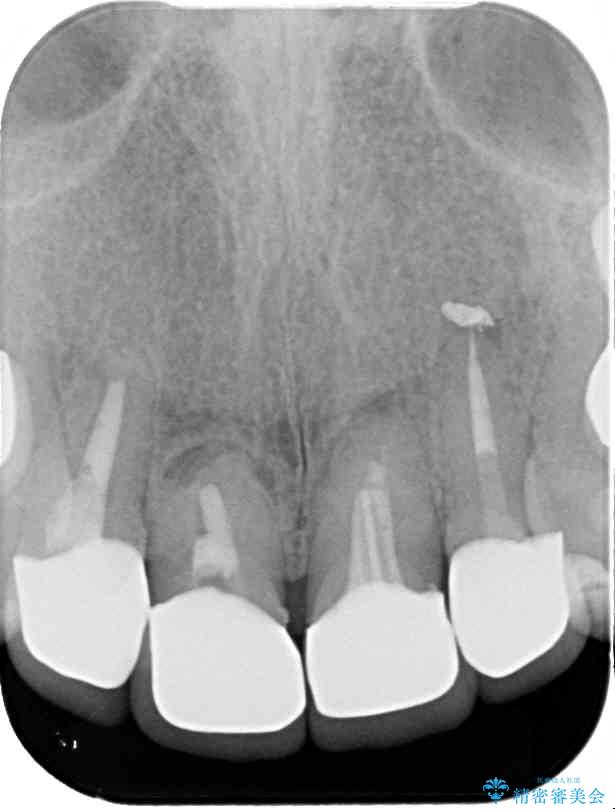

治療前

• 仮歯のまま放置した前歯 オールセラミッククラウンで自然な前歯に 治療前画像